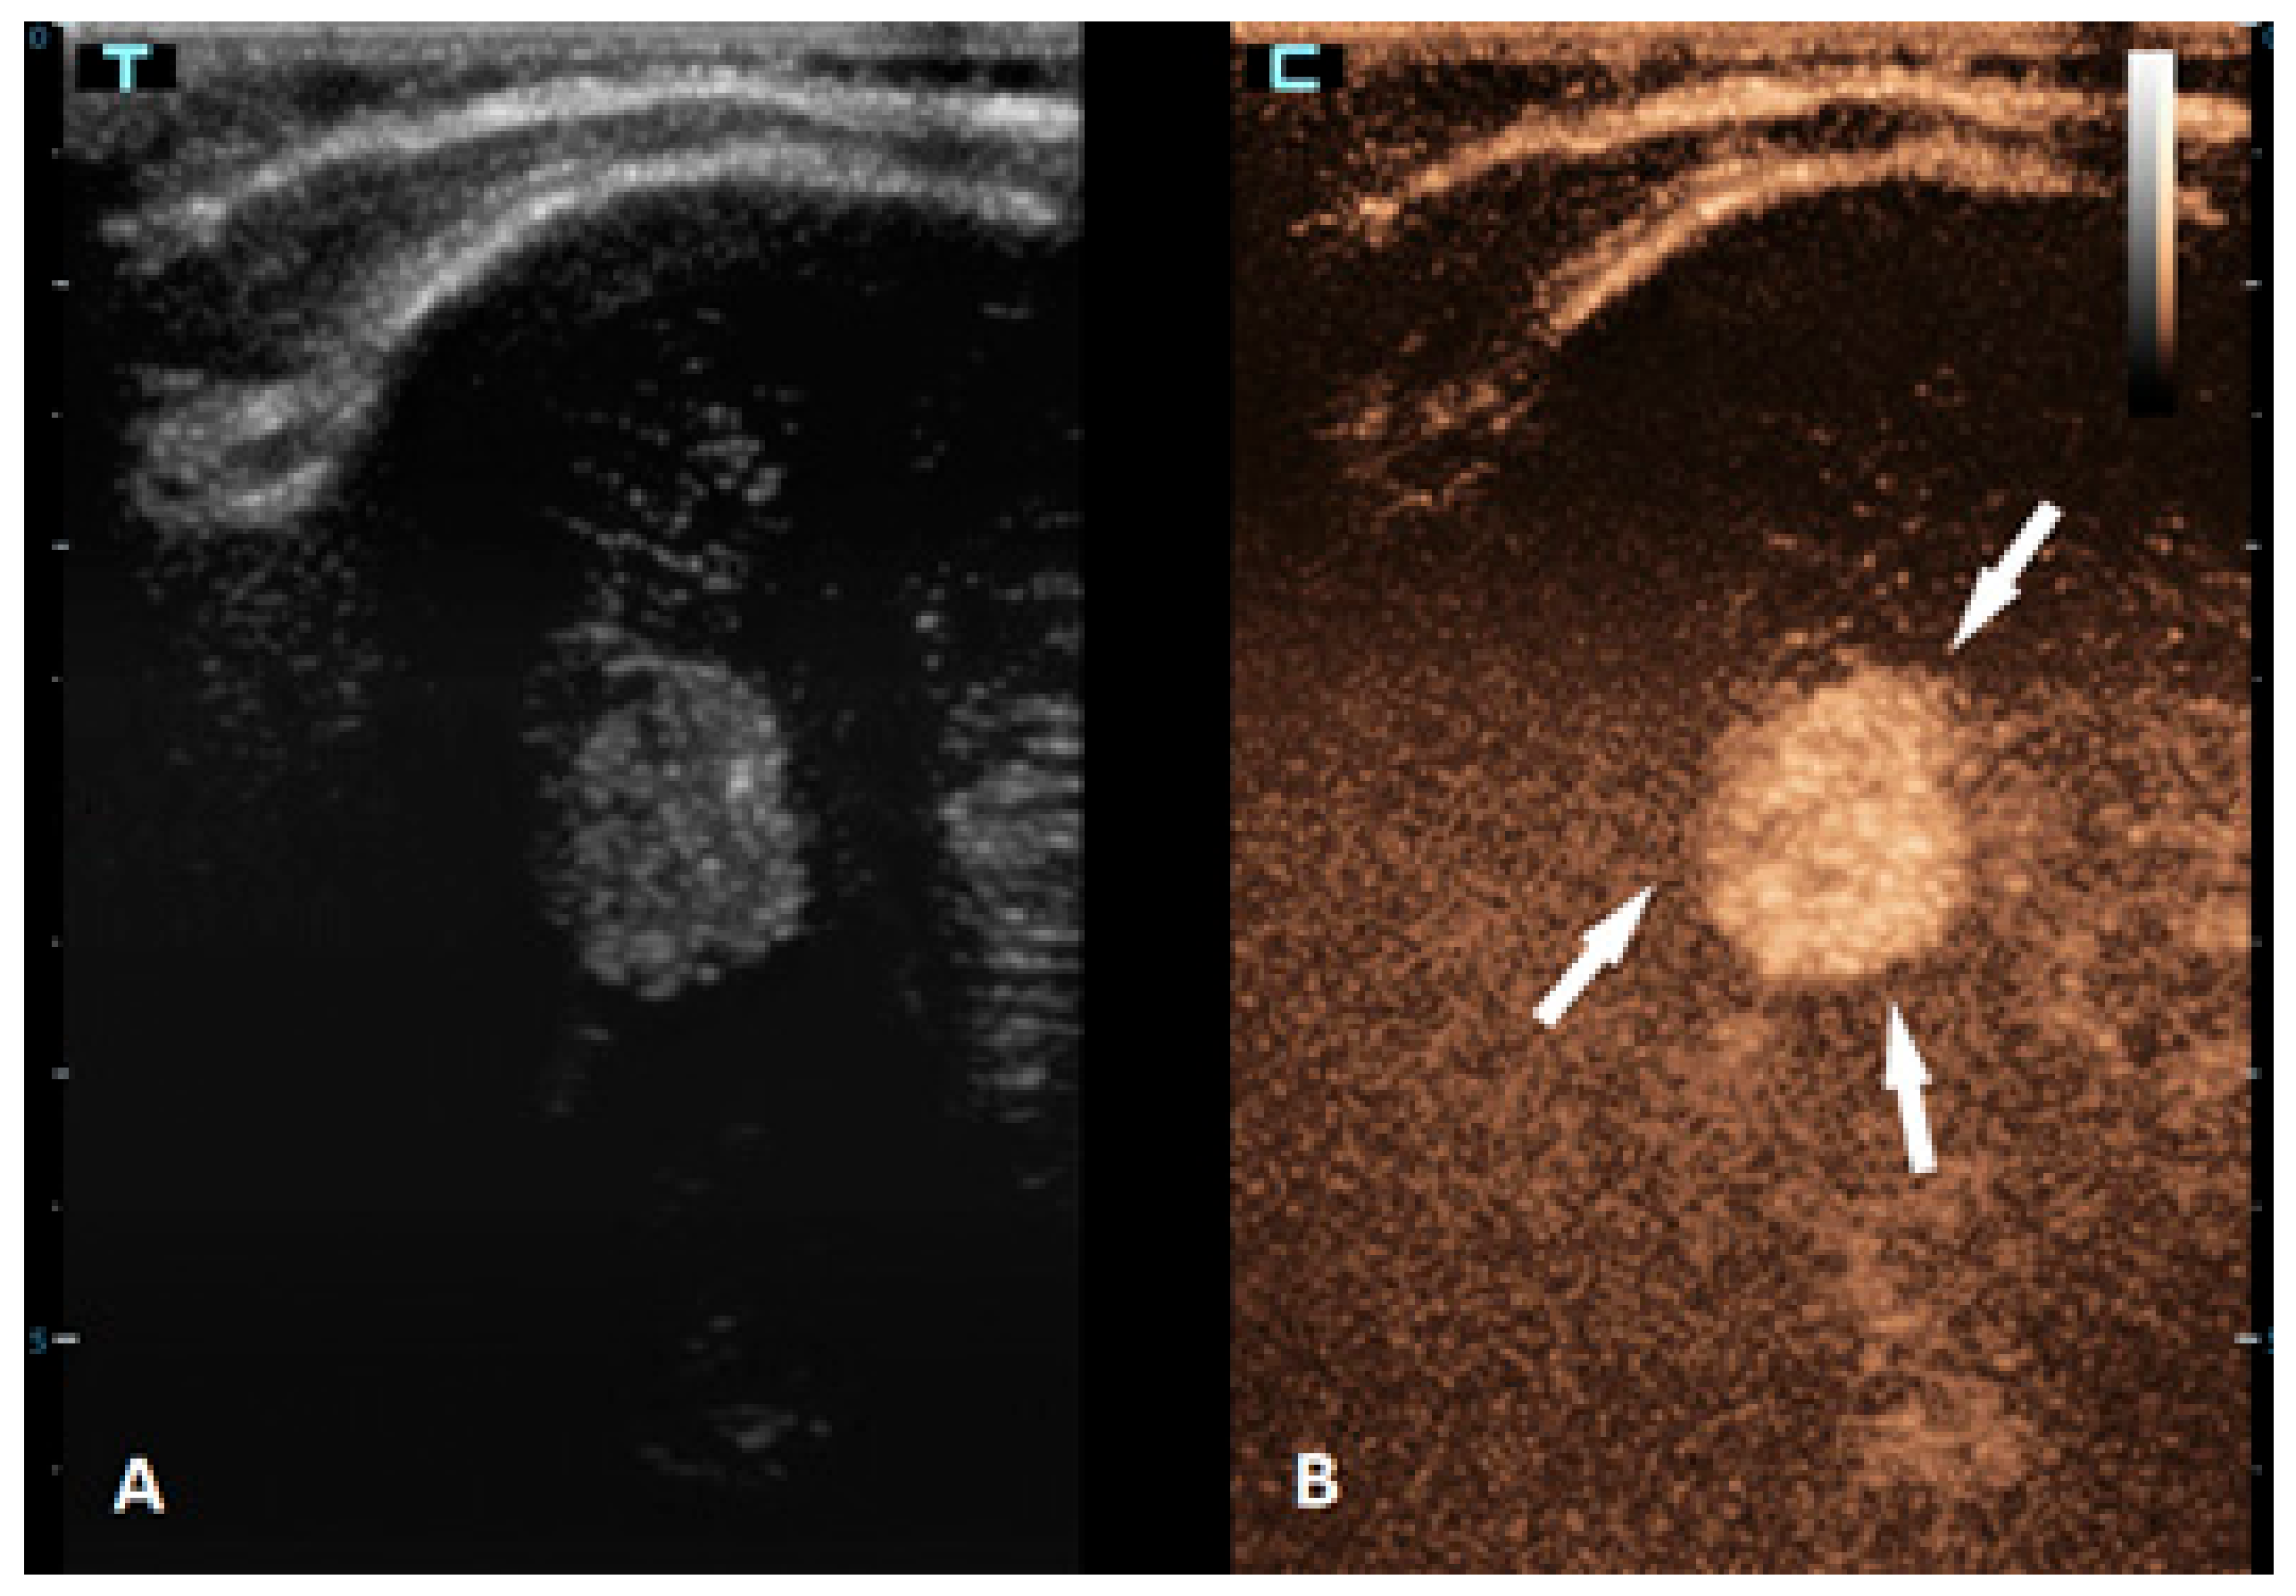

Figure 4.

A 6-month-old premature boy with an accidentally detected small lesion in the 4th ventricle. (A) The transverse reference grayscale ultrasound image through the left mastoid fontanelle. (B) The transverse CEUS image of the 4th ventricle demonstrates avid arterial and venous enhancement of the lesion (arrows). Findings were suggestive of choroid plexus papilloma; subsequent brain MRI scans confirmed benign aetiology of the lesion.

Brain tumors are the most common solid tumors in the pediatric population and are the second most frequent type of childhood cancer overall. While these tumors can occur at any age, they are most prevalent in children aged 3–7 years. Tumors in neonates and infants up to the age of 2 years typically occur in the supratentorial region, while in children older than 2 years, they are more frequently found in the infratentorial region. There are more than a hundred different histological subtypes of brain tumors that have been recognized; the most common ones are pilocytic astrocytomas, brainstem gliomas, and medulloblastomas [58]. Imaging plays a vital role in the management of patients with brain tumors. The gold standard for brain tumor assessments is MRI. Advancements in neuroimaging MRI techniques, such as the use of diffusion-weighted imaging (DWI), spectroscopy, perfusion imaging, and functional MRI, provide additional information about the metabolism and physiology of these tumors, which can aid in their diagnosis and monitoring [59]. The value of CEUS in the management of brain tumors is expanding, but the information that is available so far is still limited. CEUSs can help in the detection of solid brain tumors because they are typically more vascularized than brain parenchymas are (Figure 4). However, its ability to differentiate between different subtypes is limited [60,61]. So far, it has been most extensively used in intraoperative settings for surgical guidance [62,63]. Neoplastic tissue shows a higher contrast enhancement compared to that of the normal surrounding brain parenchyma because of its higher vessel density. Thus, CEUSs allow the most precise guidance of the surgical procedure and is especially useful for resection control [60,64,65,66].